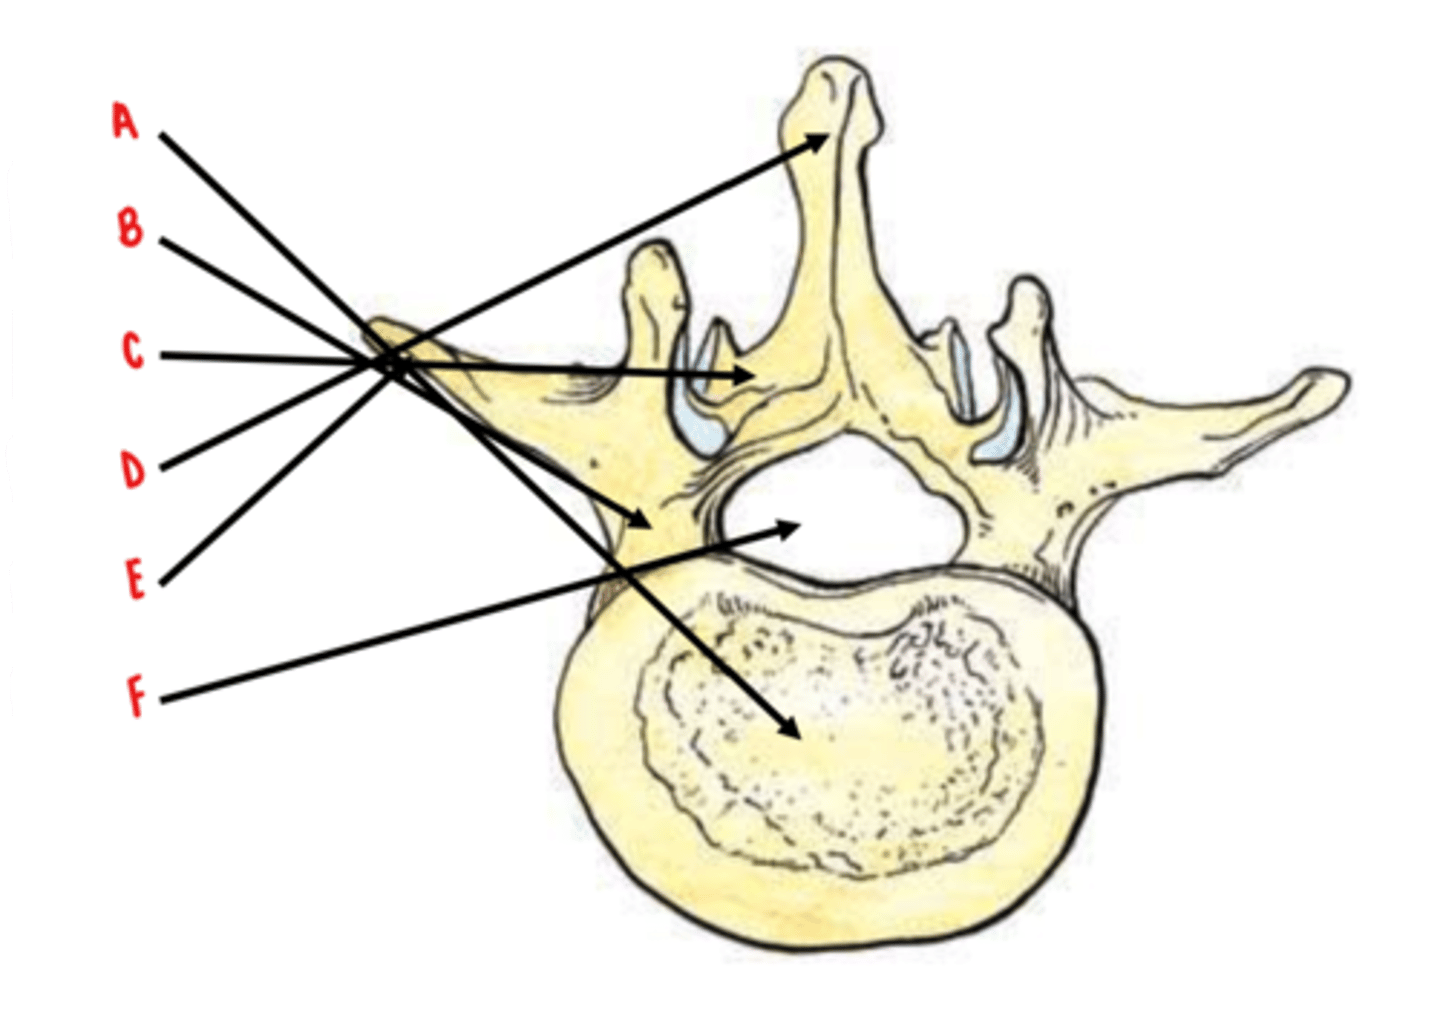

body

Identify A

pedicles

Identify B

laminae

Identify C

spinous process

Identify D

transverse process

Identify E

vertebral foramen

Identify F